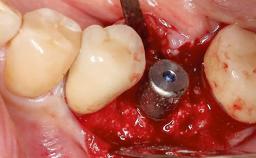

Peripheral Giant-cell Granuloma Associated with Peri-implant Tissues

Giant-cell granulomas (GCG) of the jaws are benign reactive lesions of unknown etiology, unrelated to giant-cell tumors (osteoclastomas), which are defined as benign but locally destructive and aggressive neoplasms (Jundt and coworkers 2005). Depending on their localization at the initial diagnosis, GCG are dived into central (CGCG) and peripheral (PGCG) types. CGCGs occur within the jawbones and appear as unilocular or multilocular radiolucent lesions. The incidence in the general population is very low. They are more commonly found in the mandible, mainly in children and young adults—patients are generally younger than 30 years—and have a greater incidence in females (Heithersay and coworkers 2002). The clinical behavior of CGCGs varies from slowly growing asymptomatic swellings to aggressive lesions that may result in pain, cortical perforation of the affected jaw site, and root resorption (de Lange and coworkers 2007).